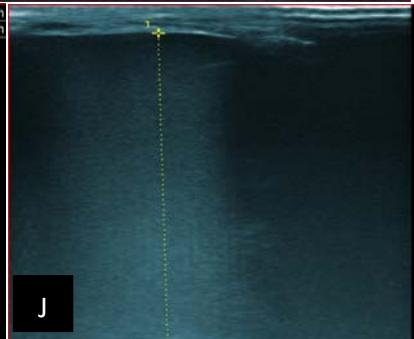

Figure 6: 9-year-old sickle cell patient, referred for abdominal bloating with significant collateral venous circulation, in whom we noted: Image A: mass, Image B: healthy renal stump, inferior polar; Image C: left transmedian extension, Image D: thrombosis of the vena cava segments: supra, retro and sub hepatic, sparing a part of the supra hepatic vena cava segment over $30~\mathrm{mm}$. Image: Ascites of great abundance, Image F: normal left kidney, Image G: splenic microcalcifications, Image H: celiac adenopathy, Image I: sub pleural pulmonary nodules with the biggest measuring $3.88 \times 3.81 \mathrm{~mm}$, Image j: left pleurisy of great abundance. Source: Dr. Frederick Tshibasu Tshienda database.